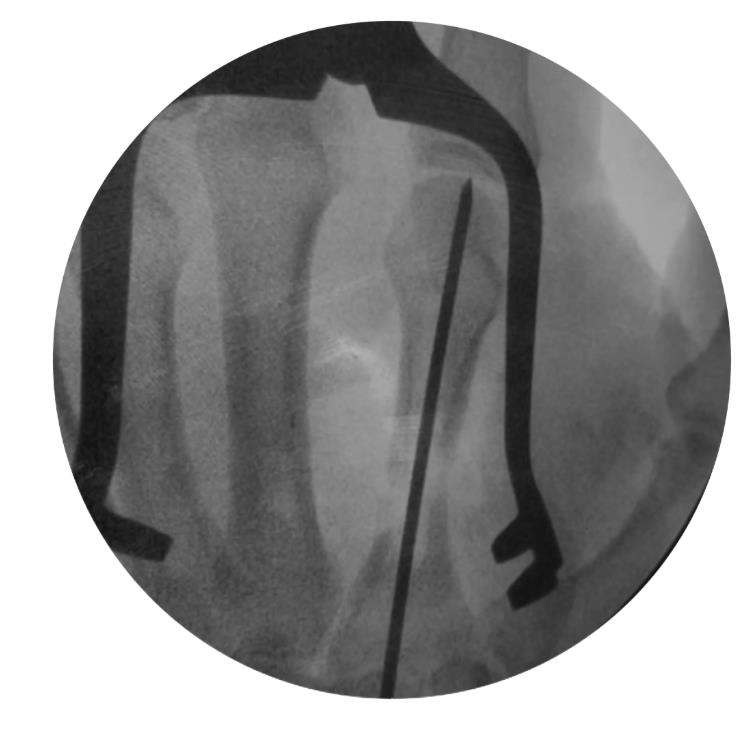

• step 1

• insert a 1.6mm k-wire into the metacarpal head and advance it to the fracture site

• reduce the fracture under fluoroscopy and advance the k-wire into the metacarpal base

• determine nail length with a measurement ruler or depth gauge and subtract 10mm from the length reading

• for the antegrade approach, flex the wrist while advancing the k-wire through the base of the metacarpal until visible

• insert the cannulated awl over the k-wire, past the soft tissues to the bone surface, with an oscillatory hand motion

• insert the cannulated awl no further than its stop, 10mm or less from subchondral bone

• step 2

• start reaming with the 2.7mm starter reamer

• sequentially ream until encountering cortical engagement, and use the reamer size that engages cortical bone to determine nail diameter

• stop reaming at least 5mm from the articular surface of the bone

• do not remove the k-wire during reaming, and use the wire pusher to keep the k-wire in position if necessary

• step 3

• assemble the drill guide by inserting the metacarpal drill guide locking screw first, aligning the drill guide tabs with the cutouts on the nail, and fully tightening

• place the k-wire tip into the cupped front end of the nail and advance the nail into the medullary canal while allowing the k-wire to exit

• confirm fracture reduction and final nail position with fluoroscopy, ensuring the locking screw holes are not near fracture lines

• retighten the drill guide locking screw after nail insertion